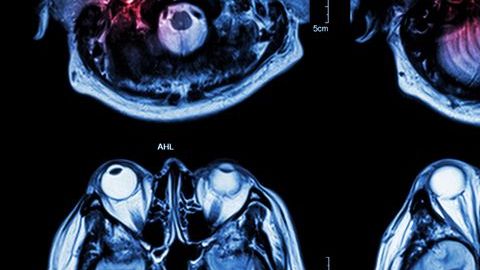

Investigan relación de derrames cerebrales con COVID-19.

Investigan relación de derrames cerebrales con COVID-19. Crédito: Shutterstock